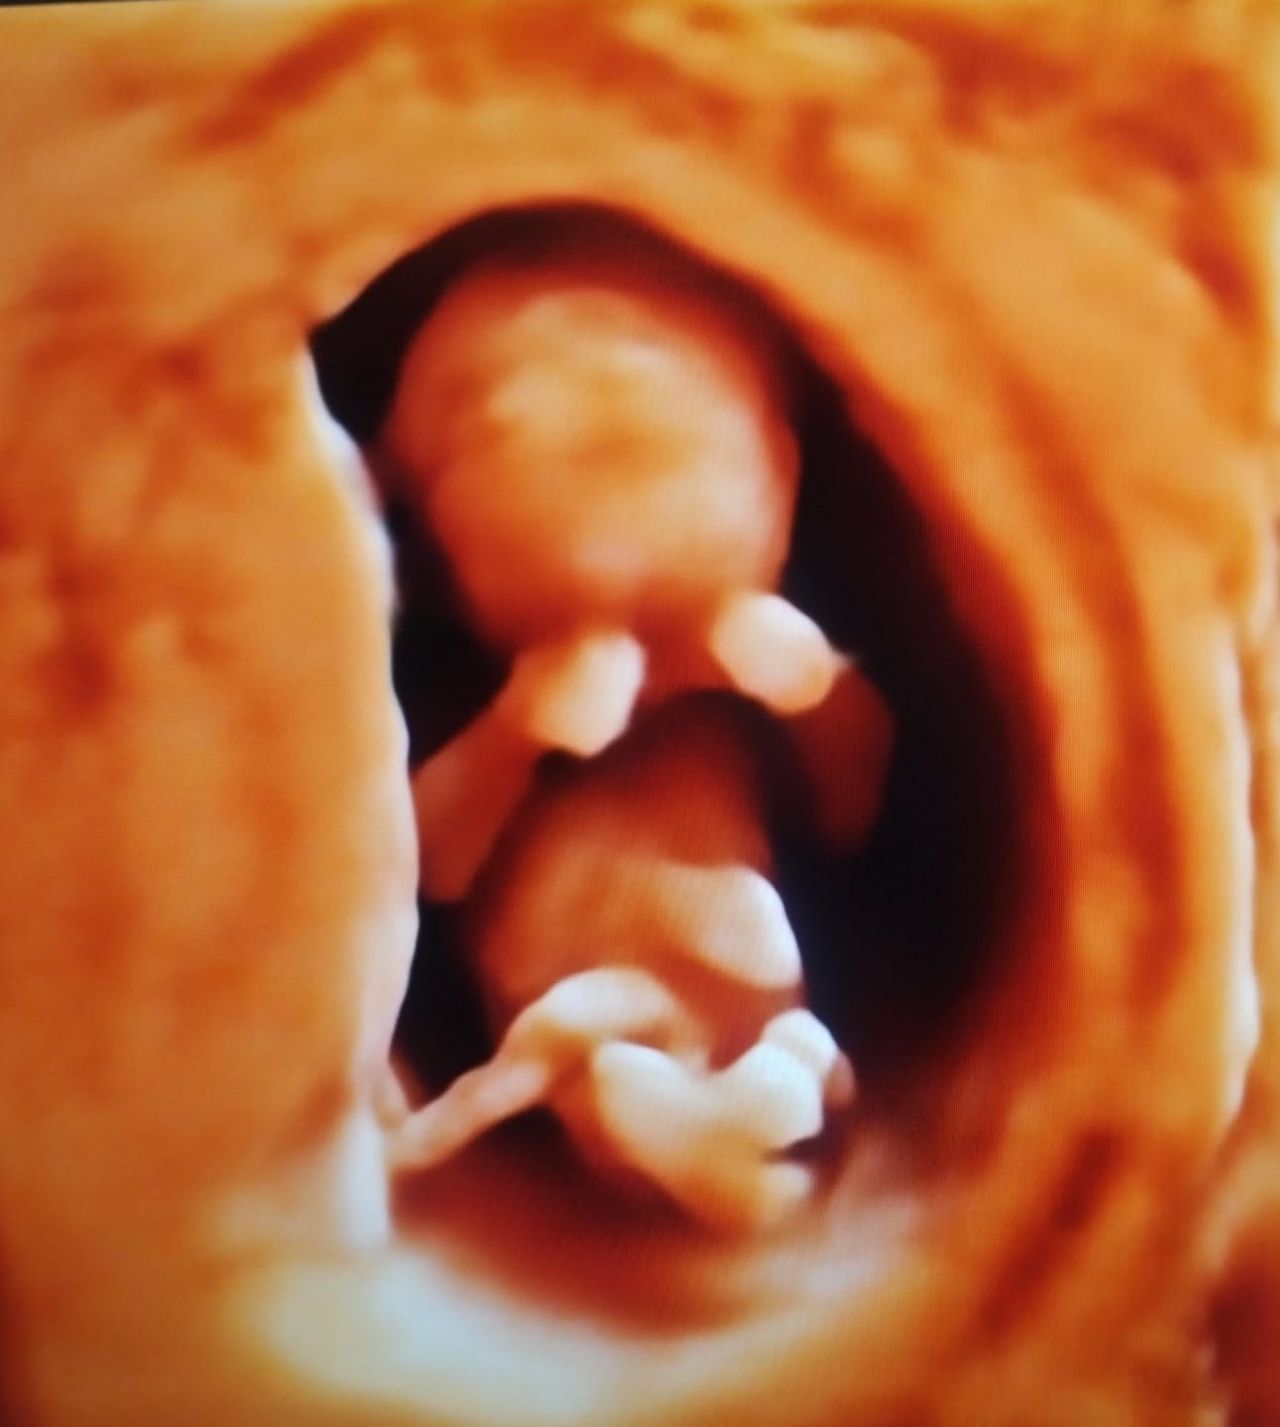

Realizamos ultrasonidos 3D y 4D obstétricos, donde puedes ver en tiempo real a tu bebe así como la evaluación Doppler para determinar el bienestar fetal.

• Ultrasonido 3D

$2,000

• Ultrasonido 4D